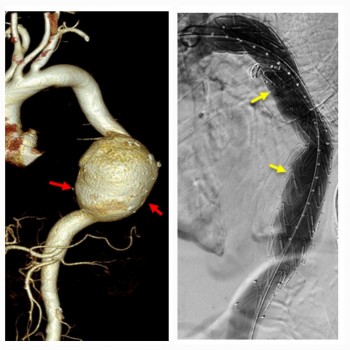

Cần Thơ: Cứu sống bệnh nhân Campuchia bị vỡ phình động mạch chủ bụng

Ngày 18/6, Bệnh viện Đa khoa quốc tế SIS Cần Thơ cho biết, các sĩ bệnh viện vừa can thiệp cấp cứu kịp thời cứu sống một bệnh nhân bị vỡ phình khổng lồ động mạch chủ bụng.